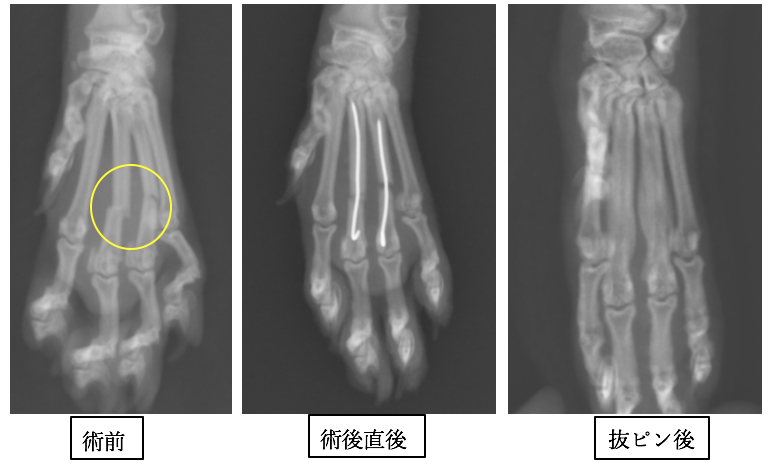

猫の中手骨骨折 動物別症例集 動物病院うみとそら 杉並区 中野区 世田谷区 土日対応の動物病院

骨折 1 猫の中手骨骨折 京都市のメイプル動物病院のブログ お知らせ

中手骨骨折 東岸和田動物病院